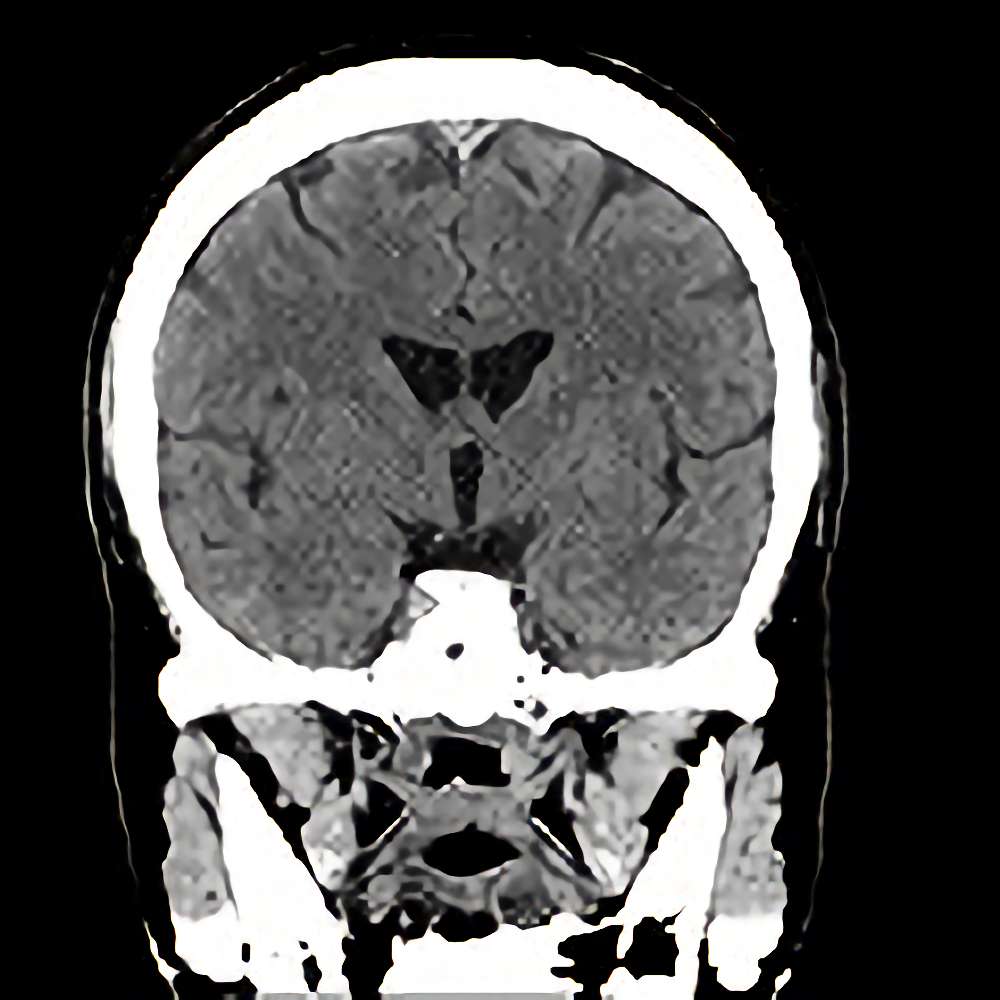

下垂体腫瘍

断層撮影

手術前1

No.’13_12 手術前1

No.’13_12 手術後